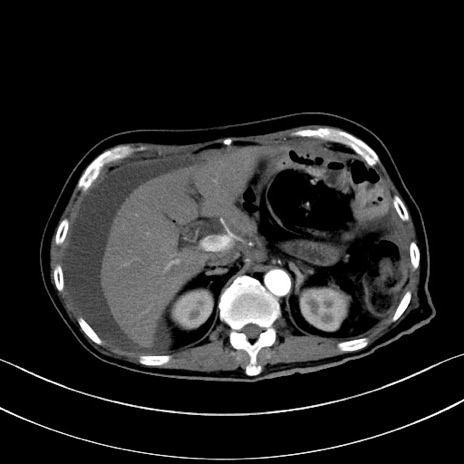

症例28(横断像)

【症例】60歳代男性

【主訴】嘔吐

【現病歴】胃癌にて胃全摘後。食思不振が悪化し、夜中に嘔吐することがある。

【既往歴】胃癌、胃全摘、脾摘、胆摘後

【データ】WBC 5900、CRP 10.56